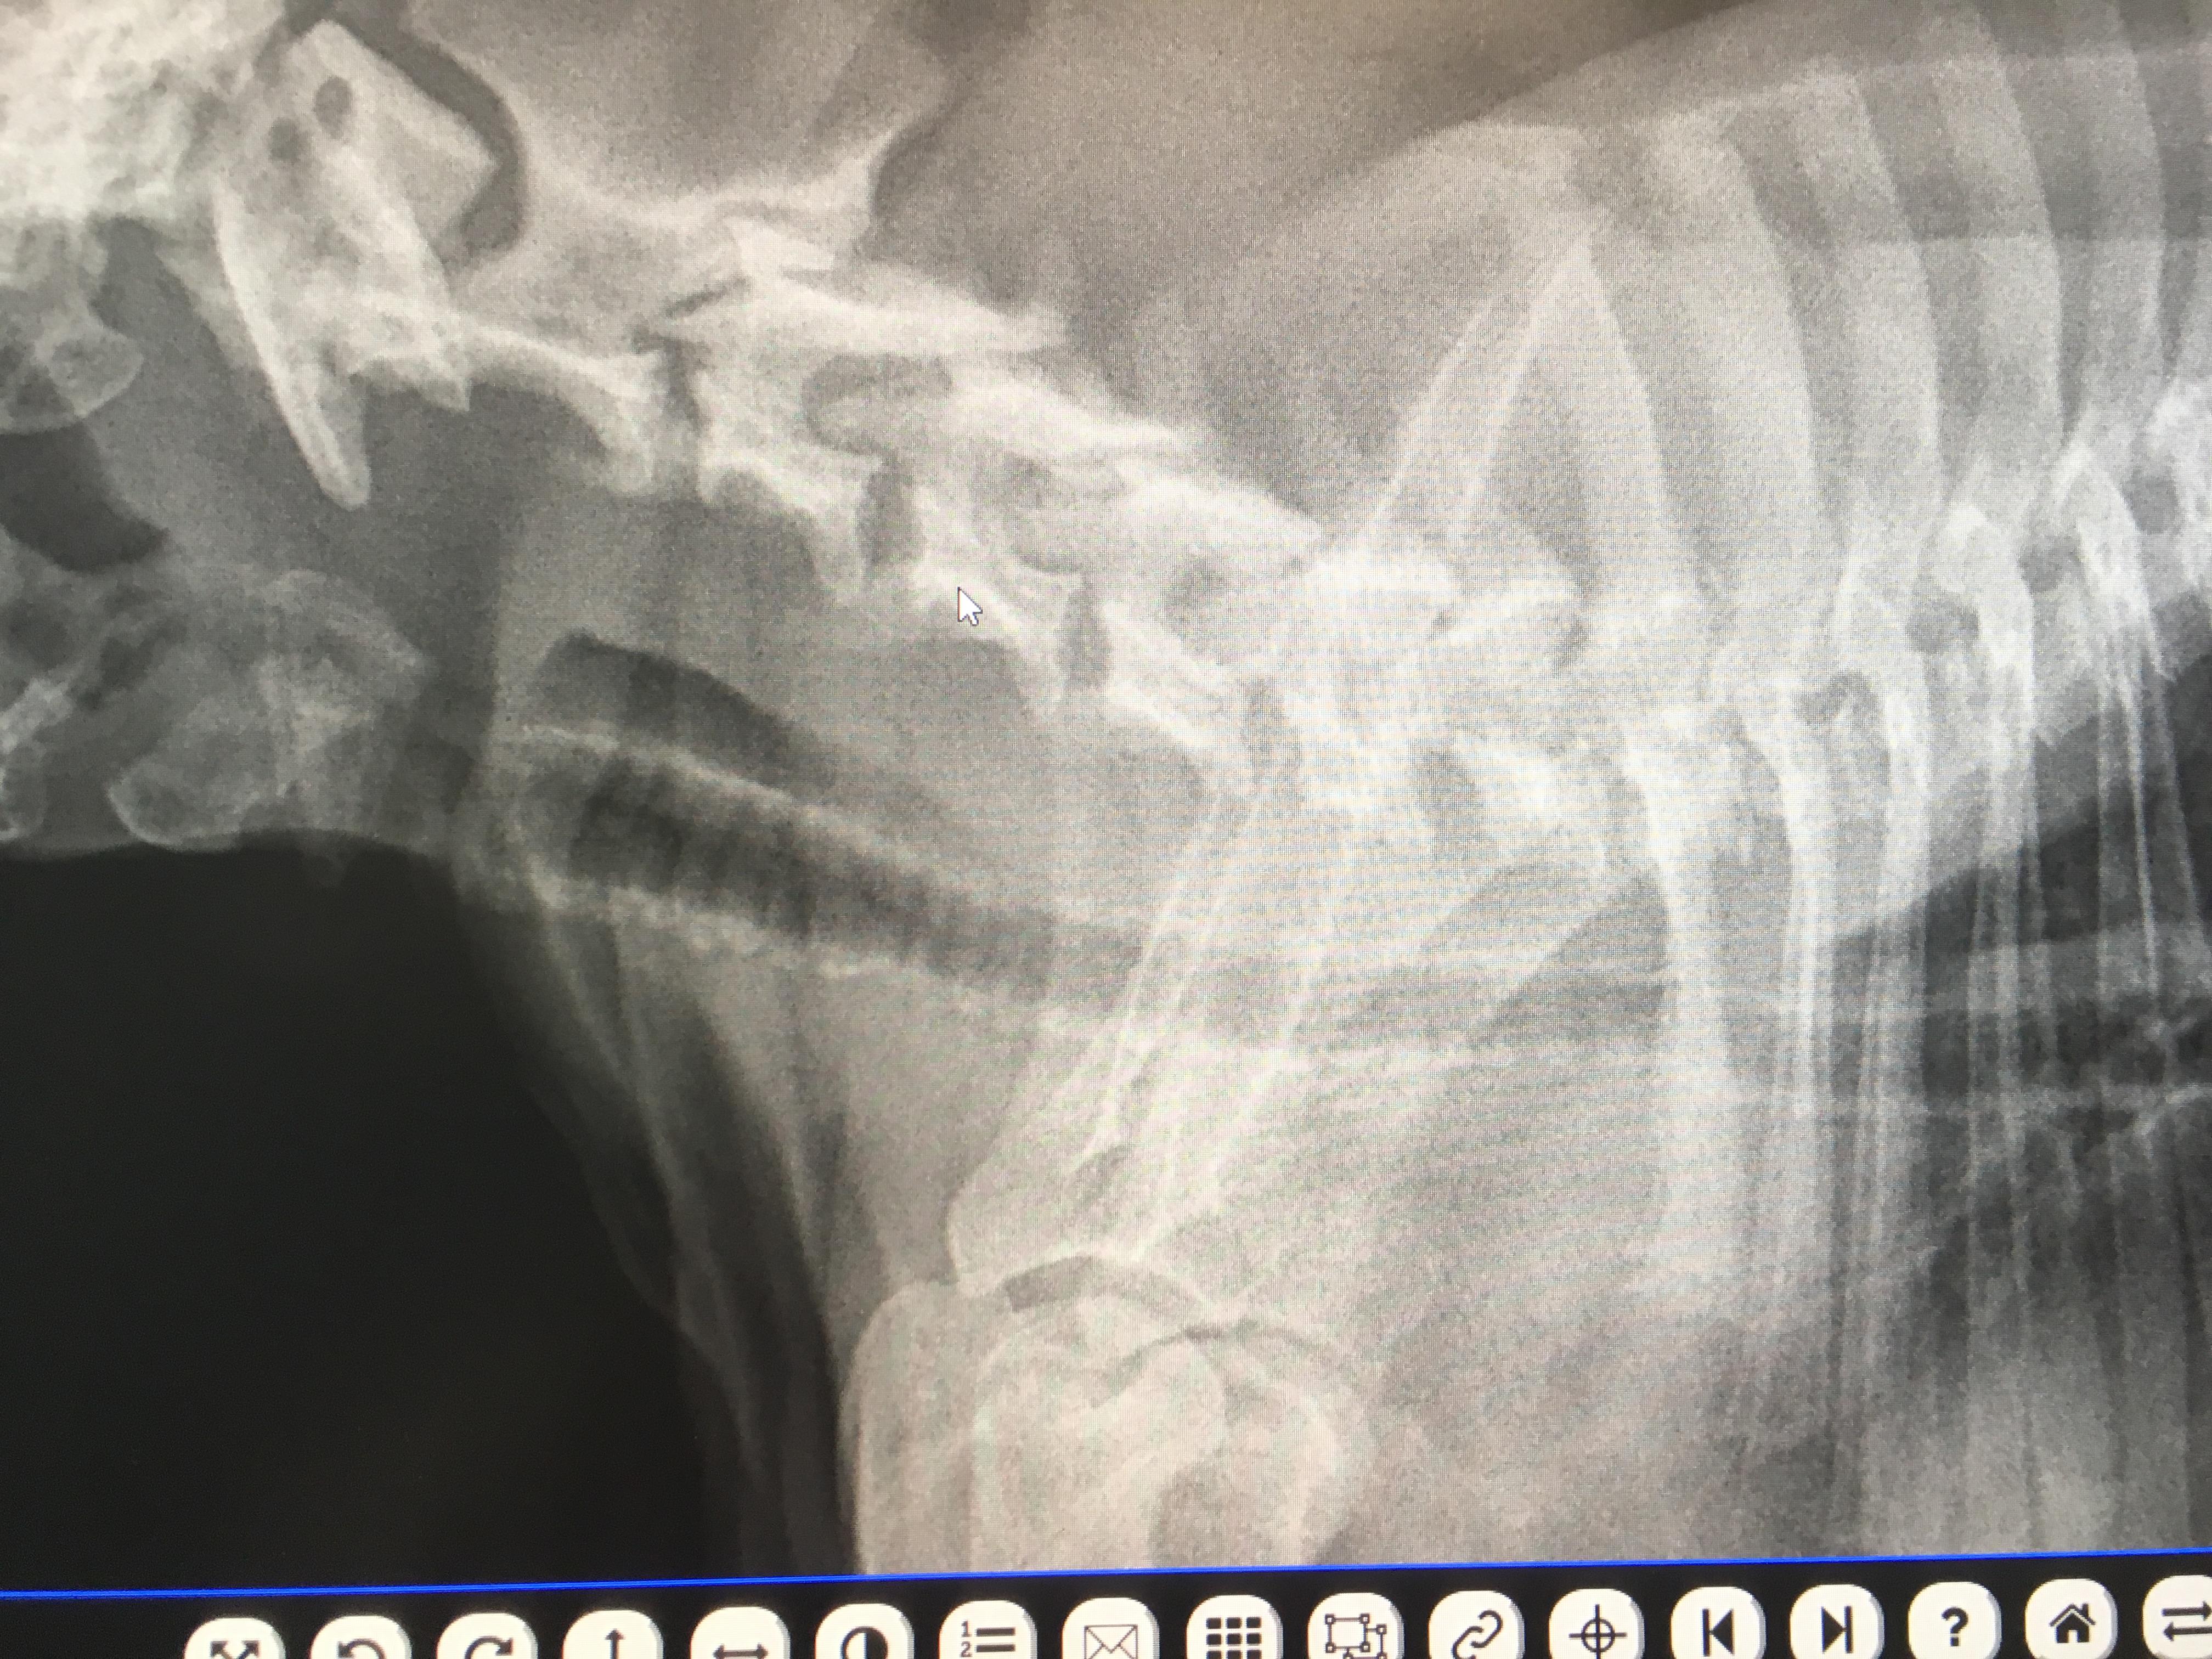

I have a 1 y/o american bully (pocket). We have had him since he was 8 wks old. Always has had labored breathing, but just attributed it to his short snout. Recently took him to a specialist due to his labored breathing appears to be getting worse. X-rays revealed tracheal narrowing with mineralizations. They said his tracheal flaps aren’t moving in their own and they want to permanently suture one flap open. Is this a common surgery? Also what could be the cause of this mineralization?

Yes, this is a pretty common surgery called a "tie back". I suggest you have it done if the specialist has recommended it. The mineralization is nothing to be concerned about - it is a very common finding although usually in older dogs. No one is quite sure why the body deposits the minerals in the tissue although it is suspected to be due to inflammation.